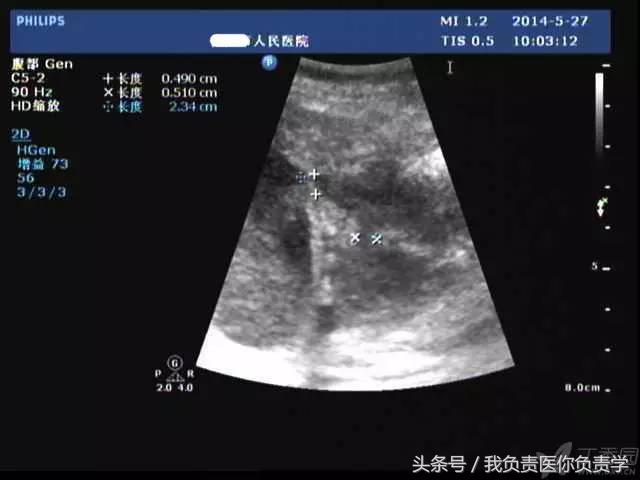

典型病例 1

患者男,64岁,因右上腹疼痛半月余就诊。查体发现右上腹部轻压痛,无发热。超声检查所见如下:

图4和5为局部放大图像,可见胆囊与囊性回声区间可见直径约2mm的通道

超声检查考虑为胆囊炎合并胆囊穿孔,后经CT检查证实。